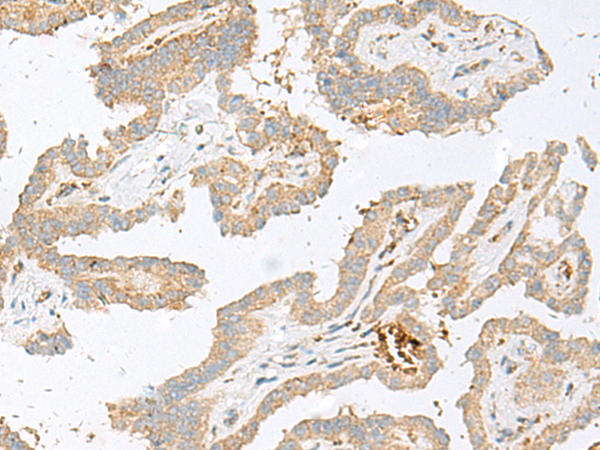

分类: 科研抗体货号: P43576别名: EIF3EIP; EIF3S11; HSPC021; HSPC025; MSTP005; EIF3S6IP应用: IHC反应种属: Human, Mouse